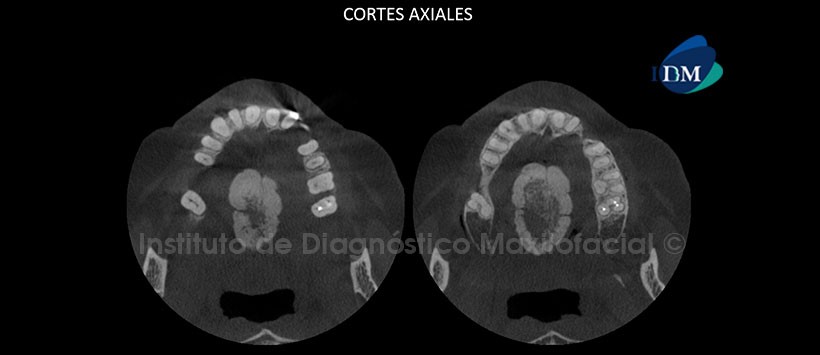

A la evaluación de la tomografía computarizada de haz cónico (CBCT), mediante cortes axiales (Figura1), cortes coronal y sagital (Figura 2), se evidencia la presencia de una excrecencia ósea de gran tamaño localizada en la parte media del paladar, de forma lobular, aspecto pediculado con una sola base amplia, donde se pueden observar varias capas: una compacta próxima al piso de la fosa nasal, otra esponjosa y finalmente una cortical muy gruesa en la periferia.

Imágenes sugerentes de torus palatino.